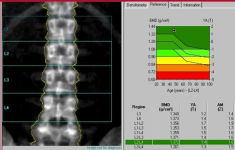

DEXA Bone Densitometry

This test (Dual Energy X-Ray Absorptiometry - DEXA) calculates the bone loss of the body, with special emphasis on the spine and femur neck thus allowing for accurate estimation of dosage to improve this condition.

DEXA is quick, painless and the preferred method to measure BMD - once osteoporosis is diagnosed, treatment can be initiated and monitored with DEXA.